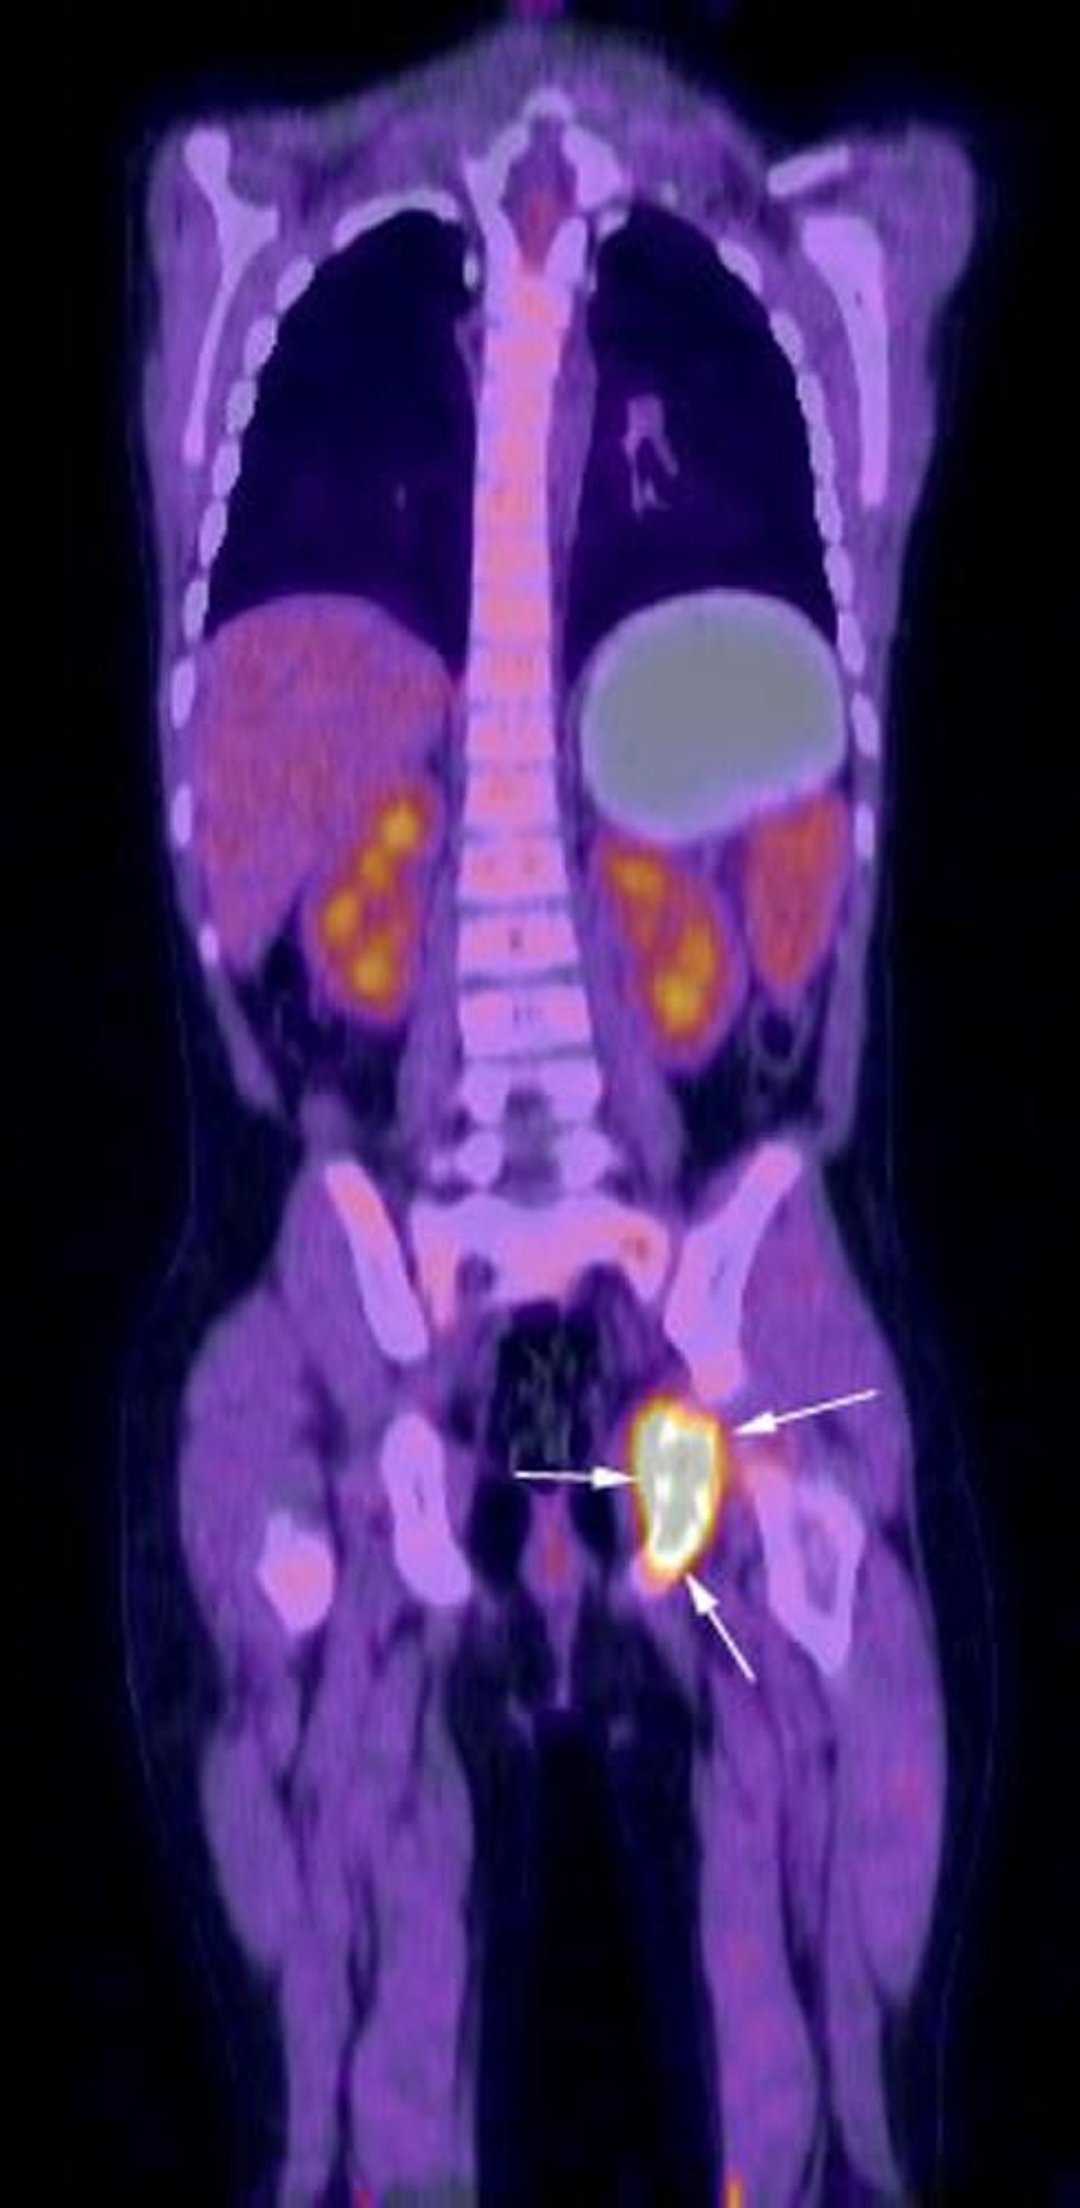

Coronal reconstruction image from FDG-PET-CT examination shows intense metabolic activity in the region of left ischium (arrows) corresponding to patient's known Langerhans cell histiocytosis.

Image courtesy of Hakan Ilaslan, MD.